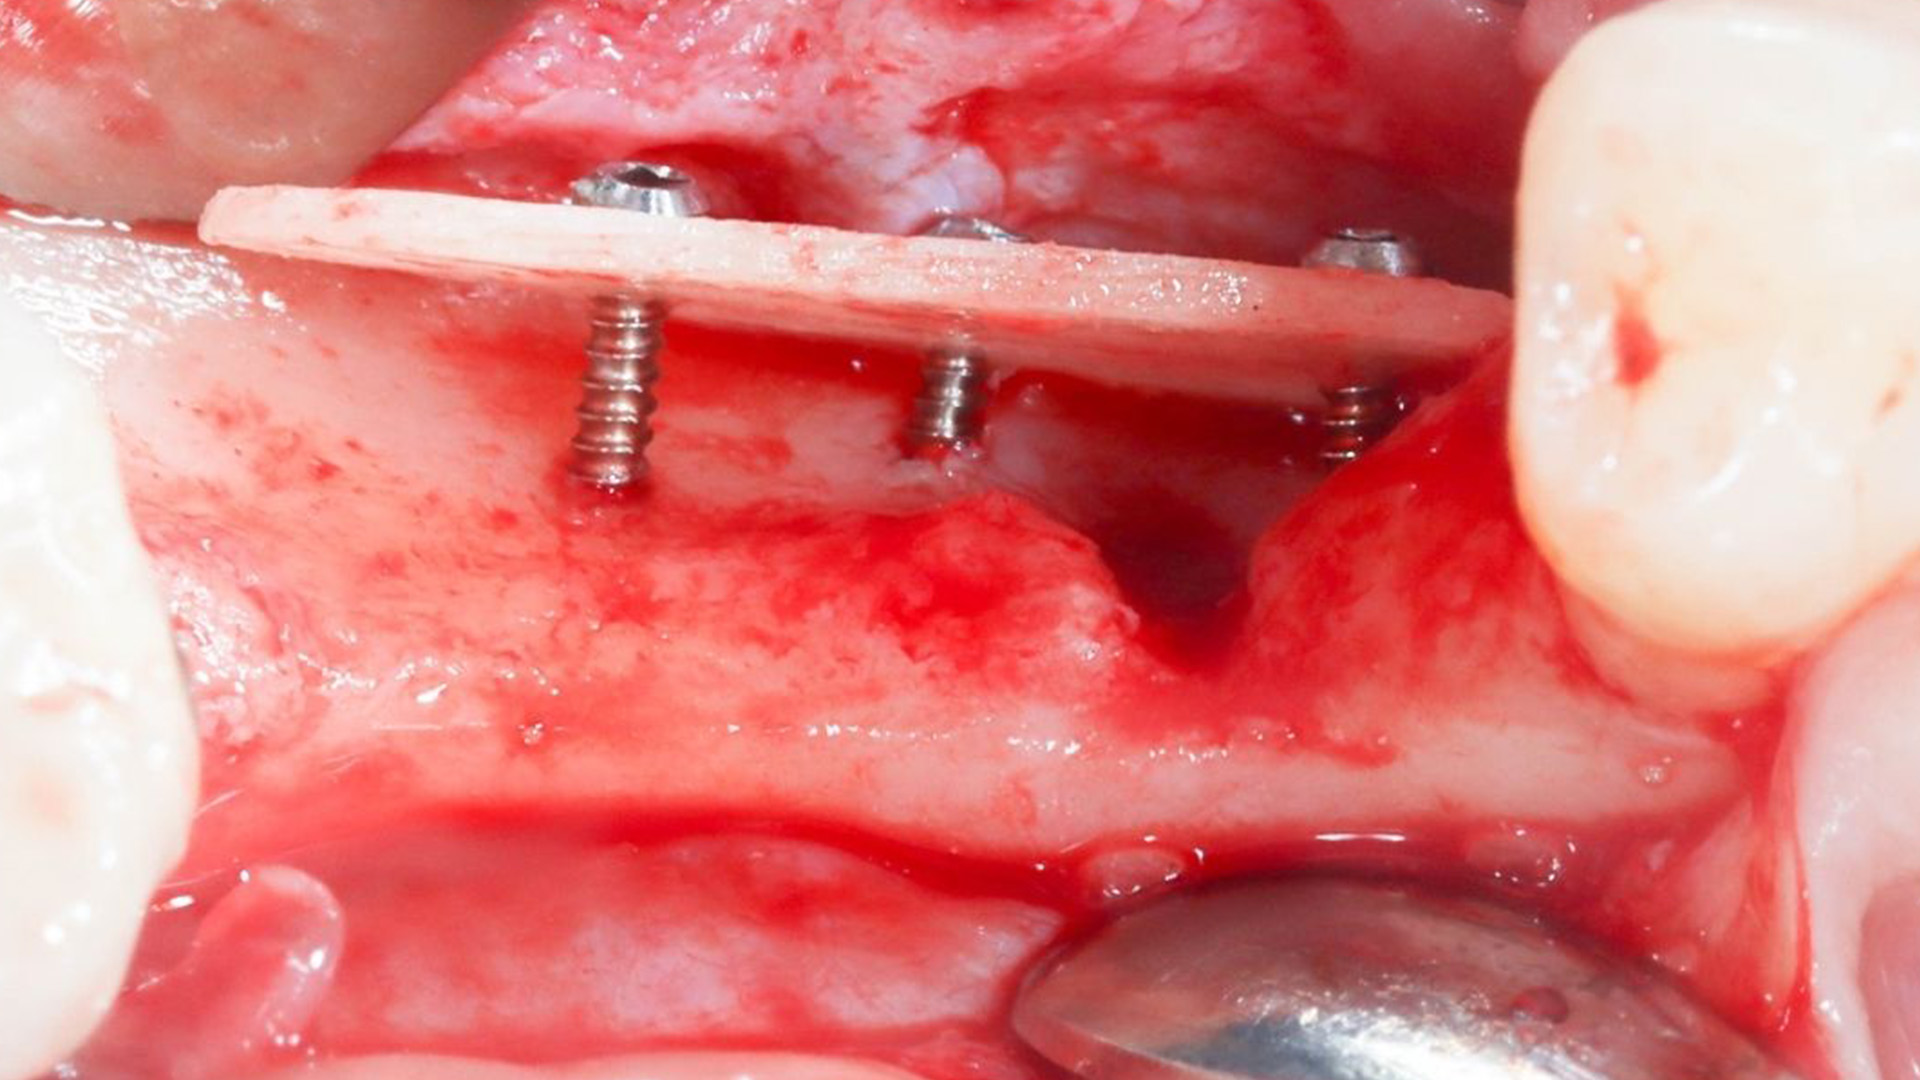

High Quality Surgical Recordings

Study high-quality surgical recordings that capture procedures step-by-step, allowing you to observe critical decision-making, tissue handling, and anatomical management in real clinical scenarios.

- Khoury | Shell Technique Using Allogenic Shell Plates (Hands On)